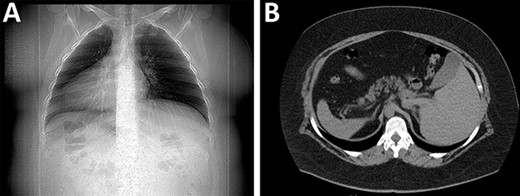

Preoperative evaluation revealed dextrocardia and that her gastric bubble was located under the right hemidiaphragm. With these findings, an abdominal computed tomography (CT) scan revealed situs inversus totalis (SIT), a condition of which she was unaware at the time. After adequate nutritional guidance, surgery was decided on this patient with a specific surgical plan for the patient’s unusual condition (Fig. 1A and B).

(A) X-rays with the organs in an inverted position. (B) CT revealing the spleen and liver in opposite places.